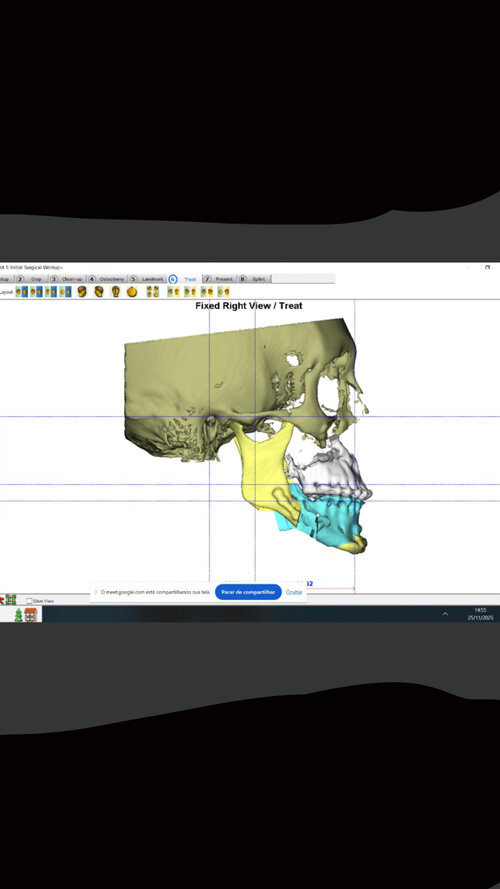

Hey guys long story short, I’m going ahead with jaw surgery revision + facial implants (low bone mass) first surgery was very conservative. I have a steep occlusion and jaw recession etc. If anyone with bimax knowledge could comment or help a niggah out I’d appreciate it ty faggets